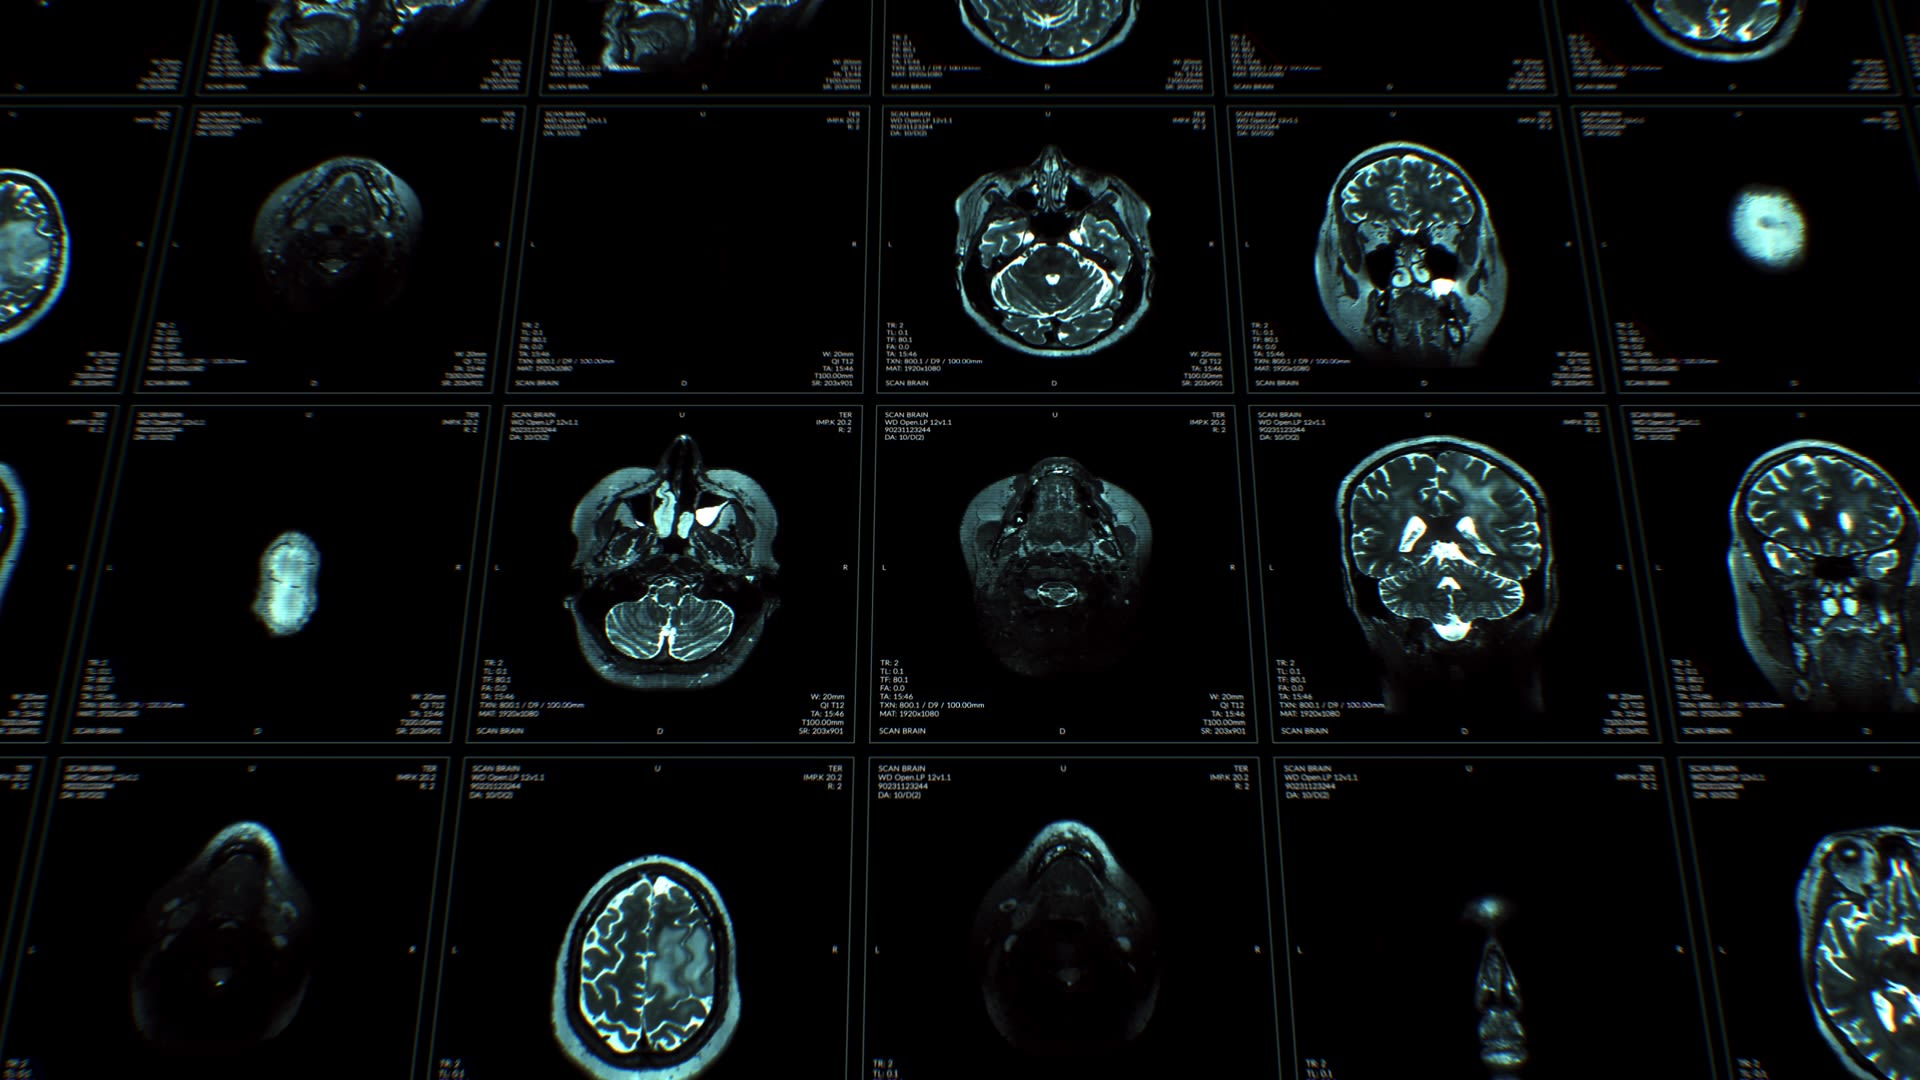

Exploring the importance of early brain development.

Mental health is not written in the stars – but some conditions can be determined even before birth and the origins of some vulnerabilities may lie in the first few months of life, says Professor Zoltán Molnár.

He says, ‘Brain development is fundamental. You are born with all the brain cells, called neurons, you will ever have.

'Most of the neurons are produced in utero, whereas some other elements of your brain, such as vasculature and supporting cells change during life.’

Professor Molnár explains. ‘We are born with all our brain cells. We carry them throughout our life. Our skin or gut cells regenerate every few weeks; we change the cells in our liver in a few months; the cells in our bones in a few years.

‘Cells in other organs divide and renew. However, brain cells don’t divide, and they don’t increase in their number. Like the eye and the nervous system, brain cells are born with you.’